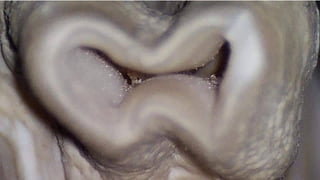

Shape of the Canals -Torabineajad

6 different shapes have been noted

1. •Round

2. •Oval

3. •Deep oval

4. •Bowling pin

5. •Kidney bean

6. •Hour glass

They include round, ribbon or figure eight, ovoid, bowling pin, kidney bean, and C shape.

With the exception of the round morphologic shape, each presents unique problems f

or adequate cleaning and shaping.

A, Round. B, Ribbon-shaped (hourglass). C, Ovoid.

D, Bowling pin. E, Kidney bean-shaped. F, C-shaped.